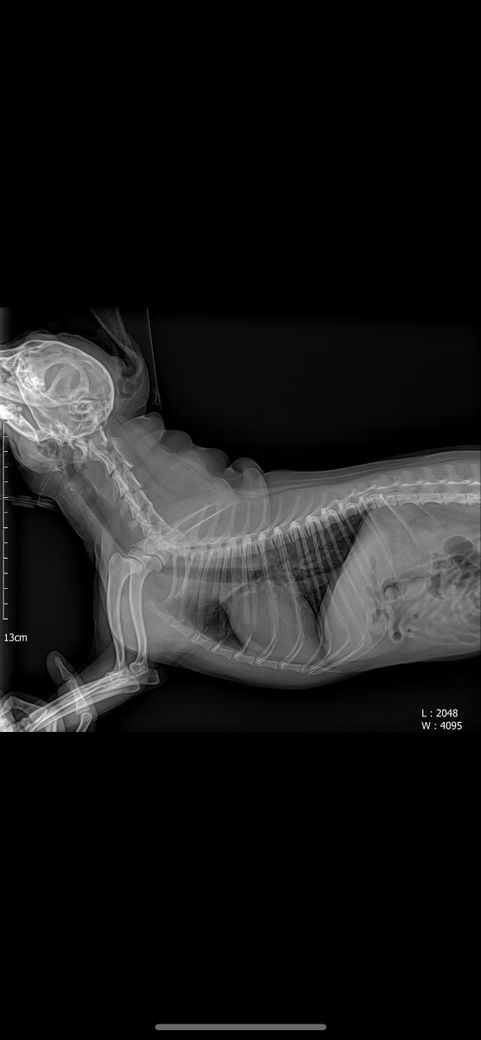

강아지 엑스레이에 문제점 있는지 봐주세요

강아지 엑스레이 문제 되는 곳 있는지 봐주세요 심장 크기랑 간이나 등등 문제 되는 곳이 있는지 궁금합니다 병원에선 문제 되는 곳 없다고 하시긴 했는데 조금 더 확실하게 알고 싶어서요

안녕하세요. 박창민 수의사입니다. 크게 문제되는 부분은 없는 거 같습니다. 또한, 엑스레이로는 정말 제한적인 정보만 얻을 수 있습니다. 더 많은 정보를 원하시면, 초음파 검사를 받으셔야 합니다. 감사합니다.

주치의의 판단이 옳은것으로 보입니다. 다만 좌측 슬개골의 내측 변위 양상 즉, 슬개골 탈구 상태가 있으니 이 부분에 대해 상담받으시고 수술 결정하시기 바랍니다.